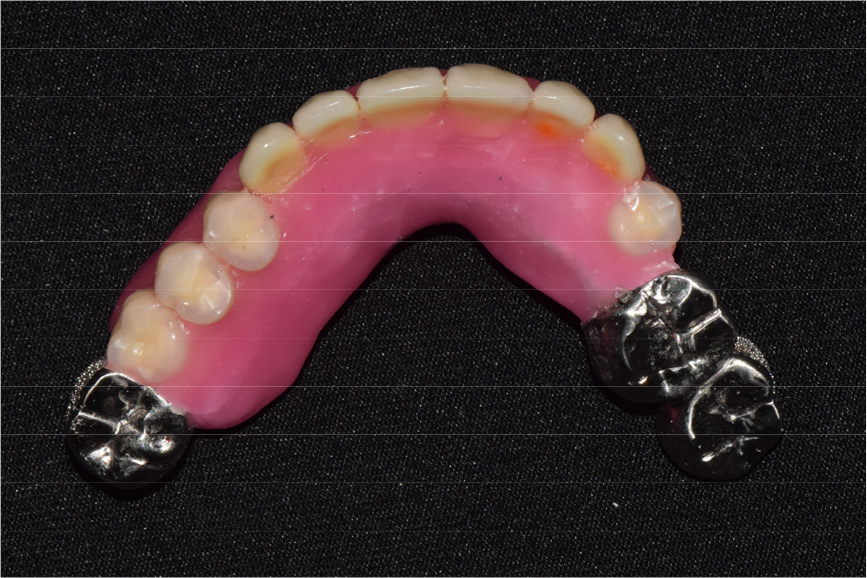

Two implants were placed in the maxillary right and left canine positions to achieve stable stress distribution in the abutments (TSIII, 4.0 × 10.0 mm; Osstem, Seoul, Korea) (Fig. 3). Intentional root canal treatment was performed on the remaining maxillary teeth to create a 4-mm interocclusal space required for the use of a hybrid telescopic double crown. For definitive prosthesis fabrication, a silicone impression was made using polyvinyl siloxane (Aquasil Ultra XLV and Aquasil Ultra LV; Dentsply Sinora, Philadelphia, PA, USA) for the maxillary implants and teeth using an individualized tray (Fig. 4). The inner crown, outer crown, and metal framework of the final prosthesis were made of Co–Cr alloy (VeraBond 2V; Aalbadent, Fairfield, CT, USA) (Fig. 5).14 For each abutment and implant, the spark erosion method was used to form a channel of approximate diameter under 0.8 mm for placing the friction pin in the mesial or distal region. A friction pin was installed in this channel to obtain a retention force. The axial convergence angle of the inner crown was set at 2 degrees, and a chamfer margin was designed to prevent movement between the inner and outer crowns. Laser welding was used to join the outer crowns to the metal framework, and artificial teeth were arranged using the group function concept on the metal framework for the wax trial dentures (Fig. 6). The vertical height and centric position of the trial denture were reconfirmed with the patient’s consent after the try-in process in the oral cavity, and a definitive prosthesis was fabricated. Glass ionomer cement was used to fix the inner crown (Fuji I; GC, Tokyo, Japan).